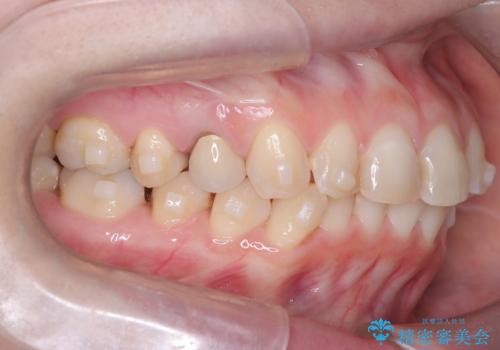

- 下の前歯のデコボコ(叢生)を気にされてご来院されました。精密な検査の結果、下の前歯を並べるスペースが不足していることが判明。患者様のご希望から、透明で目立ちにくい**インビザライン(マウスピース矯正)による治療計画を立案しました。主に歯の側面をわずかに削るIPR(歯間乳頭保護下ストリッピング)**などでスペースを確保し、下の前歯の叢生を解消することを目指します。

今回の矯正治療では、透明なマウスピース型の装置インビザラインを使用しました。目立たず、取り外しが可能なため、日常生活にほとんど影響なく治療を進めることができました。治療は、緻密に計算された計画に基づき、IPRなどで必要なスペースを確保しながら、下の前歯をスムーズに移動。これにより、長年の悩みであった下の前歯のデコボコが解消され、清掃しやすい、整った歯並びを獲得していただけました。